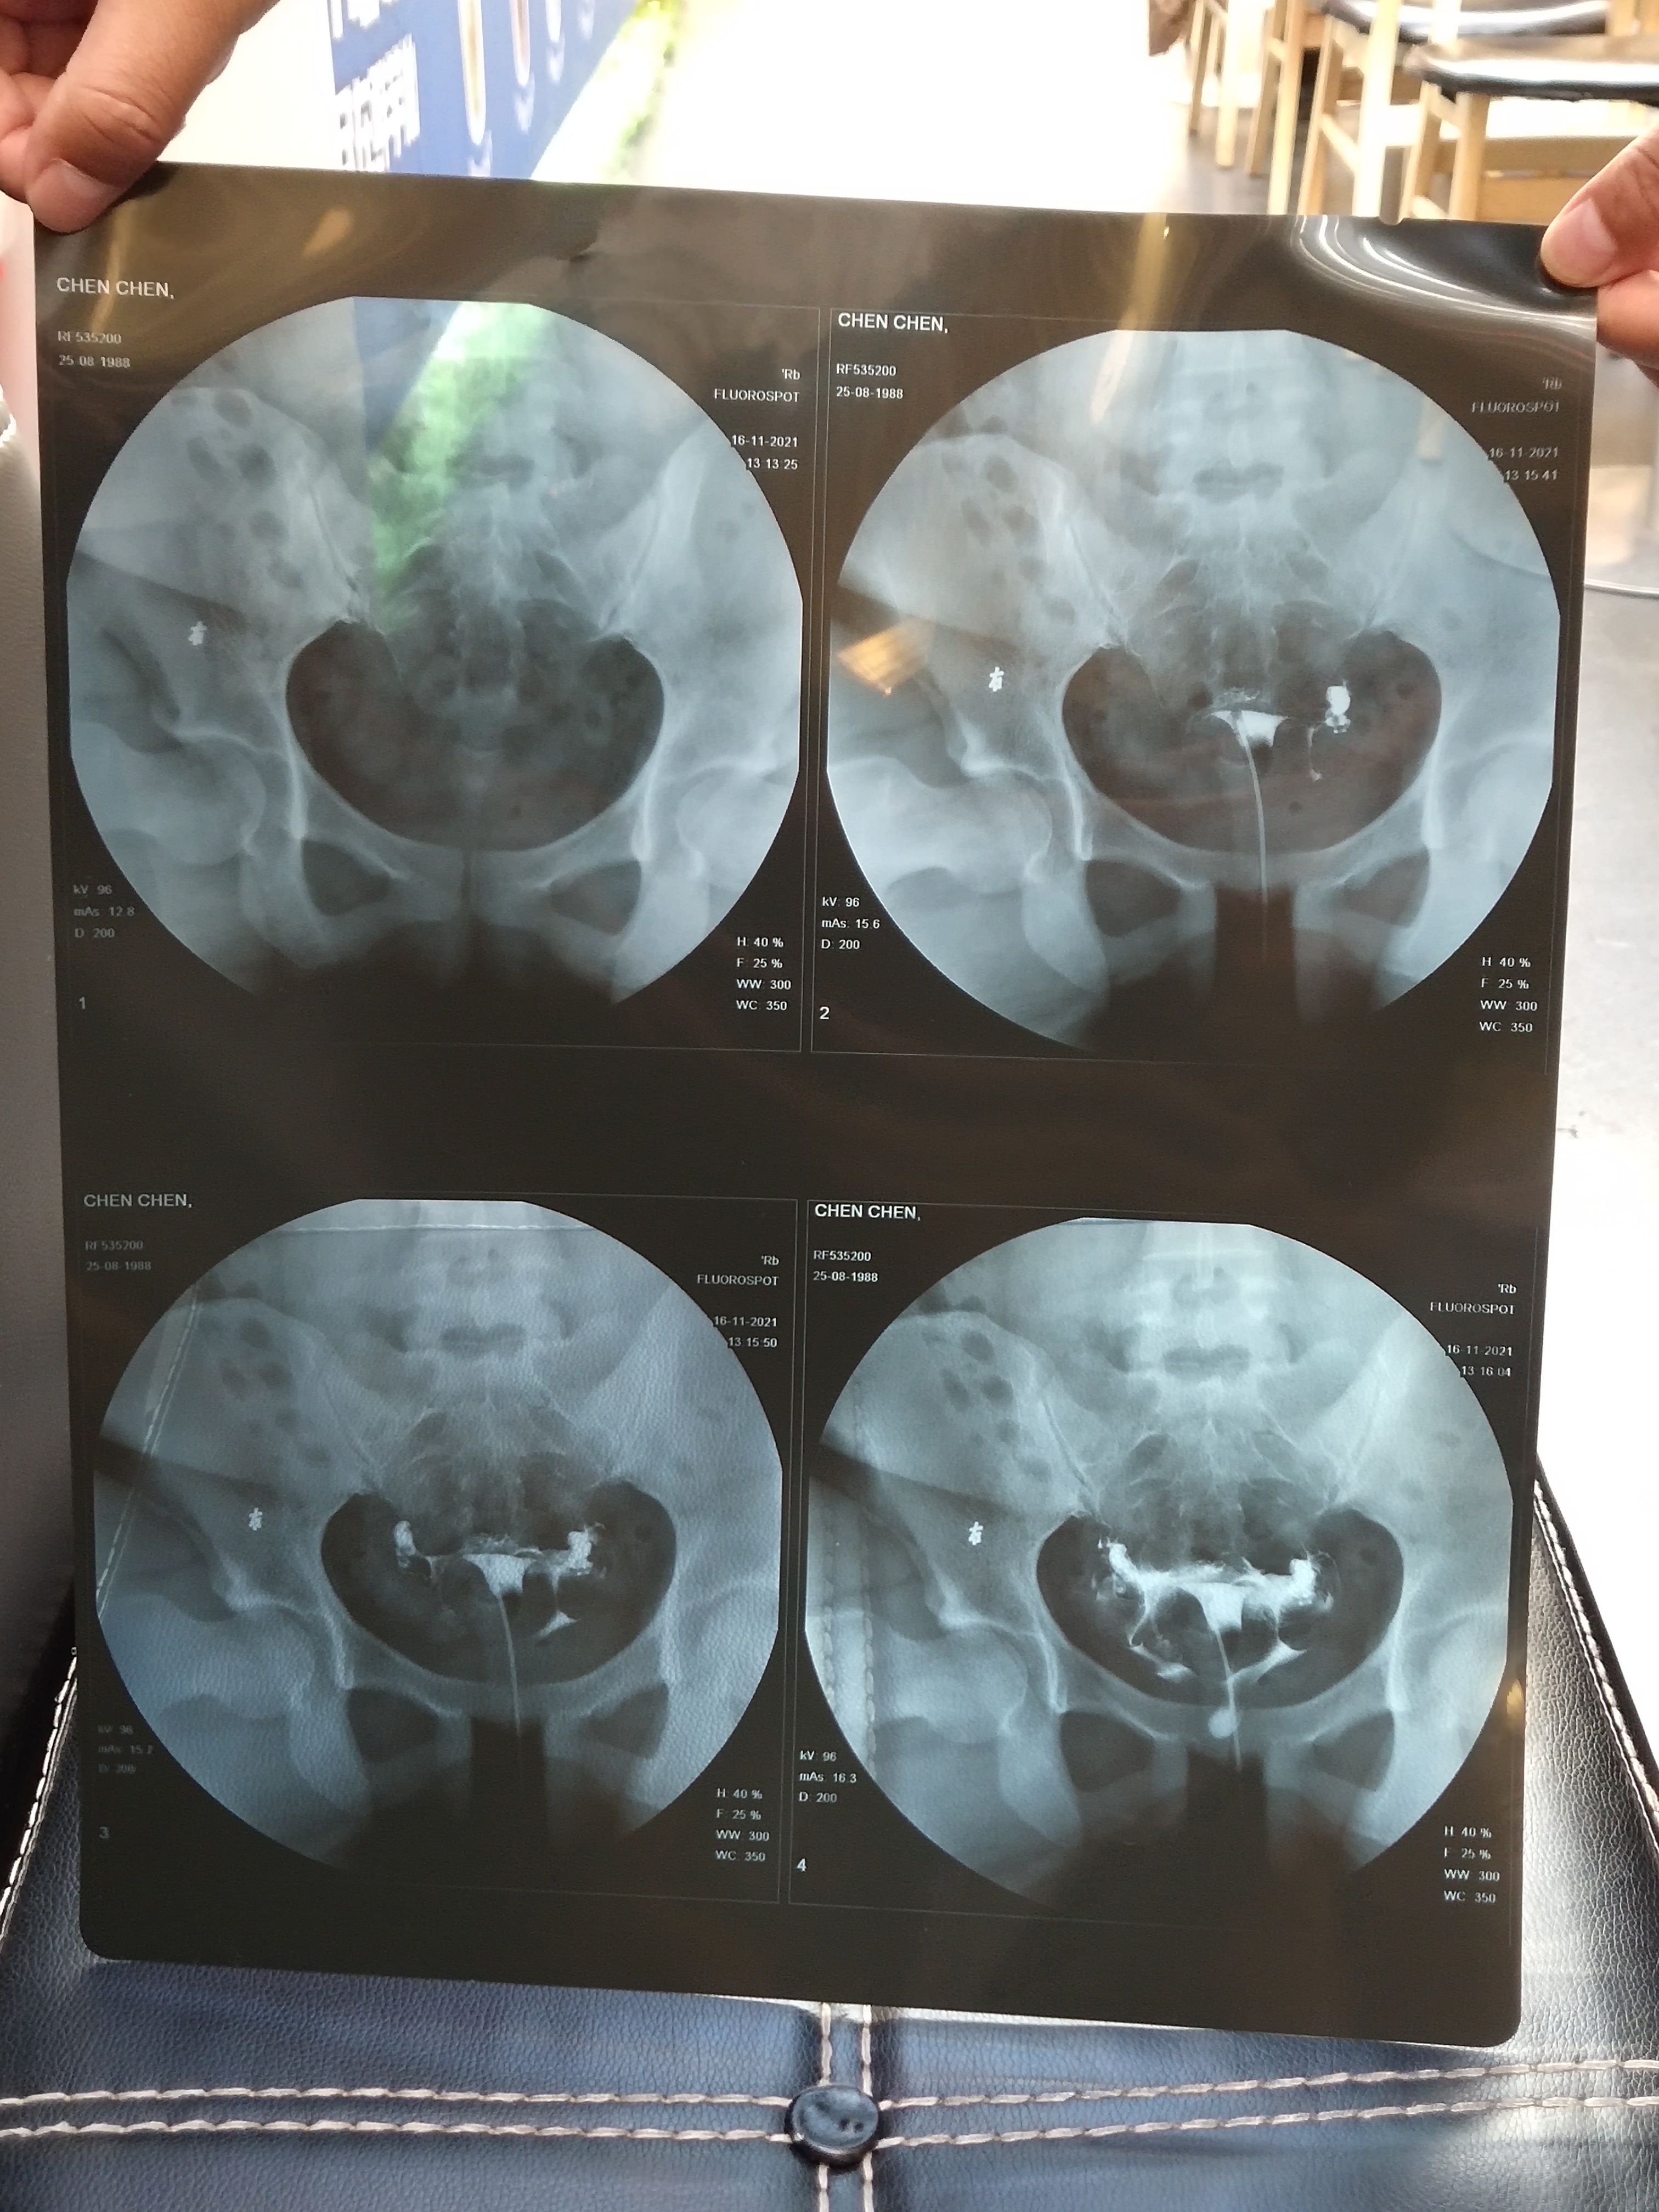

医生说我输卵管粘连,建议做试管婴儿,无法疏通输卵管。想请问还有自然受孕的可能吗?